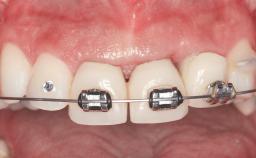

Replacement of Four Incisors with a Fixed Partial Denture on Two Narrow-Neck Implants after Implant Failure

| Prosthesis Type | FDP |

| Loading Protocol | Conventional or early |